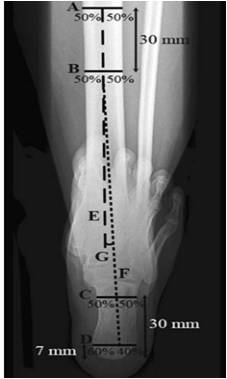

后足长轴位 1. 确定胫骨长轴E 2. 确定跟骨长轴F – 距跟骨最低处7mm处做水平线C,分为3:2 – 距跟骨最低处30mm处做水平线D:分为1:1 |